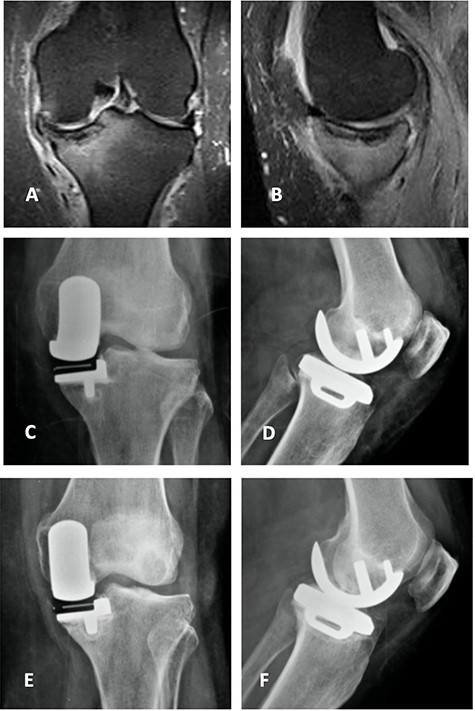

Orthostatic anterior view (A) and Rosenberg (B) X-ray images with medial osteoarthritis—right knee; Lateral view X-ray image of the same knee (C); T2 coronal MRI (D) with severe MP and femoral condyle SIFK; Immediate postoperative X-ray image (E) and 3 months after surgery (F) showing tibial component loosening.